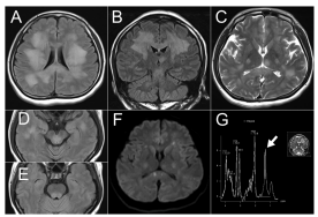

脑部MRI影像显示 双侧大脑半球白质、脑白质、脑白质及右侧中脑梗中广泛T2及FLAIR高信号病变 (图1A-E), 部分病变包含扩散受限区域 (图1F);

质子磁共振光谱显示 白质病变中乳酸峰强度增加 (图1G)。

图1 A-E脑部MRI显示双侧大脑半球、脑白质、脑白质中弥漫且大致对称的T2和FLAIR高信号病变(A、B、D、E、FLAIR; C、T2加权图像)

存在小区域的限制扩散(F,扩散加权图像)。1H磁共振光谱显示大脑白质病变中乳酸峰强度增加(G,箭头)